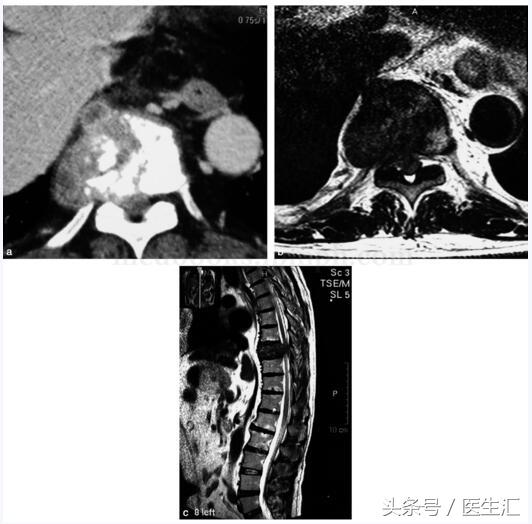

图21‐2 CT 及MRI 示胸9 椎体骨质破坏,软组织肿块形成并向右后方突出,相应水平椎管狭窄,胸髓受压变形

影像学检查:全身骨扫描示右侧第7 前肋及第9 胸椎放射性异常浓集,骨骼其余部位未见转移性病灶(图21‐1)。CT 示第9 胸椎体溶骨性破坏,局部可见软组织肿块。MRI 示第9胸椎体骨质破坏,软组织肿块形成并向右后方突出,相应水平椎管狭窄,胸髓受压变形,与肿物分界不清,增强扫描后见肿物强化明显且不均匀(图21‐2)。